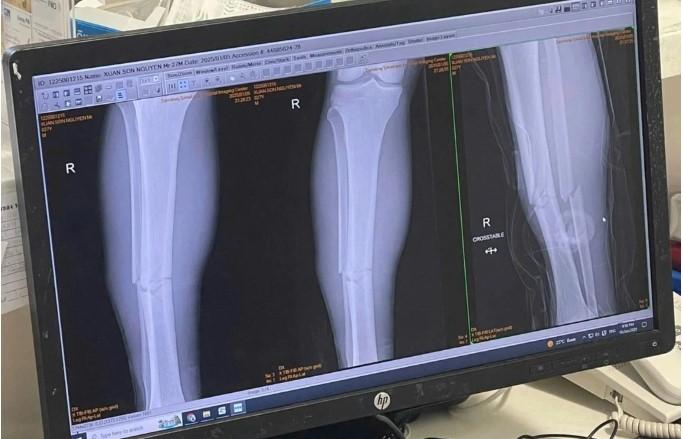

Phim chụp chấn thương của Xuân Son.

Bác sĩ Thi đã xem phim chụp chân của cầu thủ Nguyễn Xuân Sơn và thấy ổ gãy khá vụn.

“Thời gian phục hồi chấn thương của cầu thủ Nguyễn Xuân Son phải mất tối thiểu 6 tháng trở lên để có thể đá túc tắc trở lại được. Tuy nhiên, cầu thủ cũng chỉ đá được 60%, còn để thi đấu đỉnh cao, trong thời gian dưới một năm là ít khả năng”, bác sĩ Thi dự đoán.